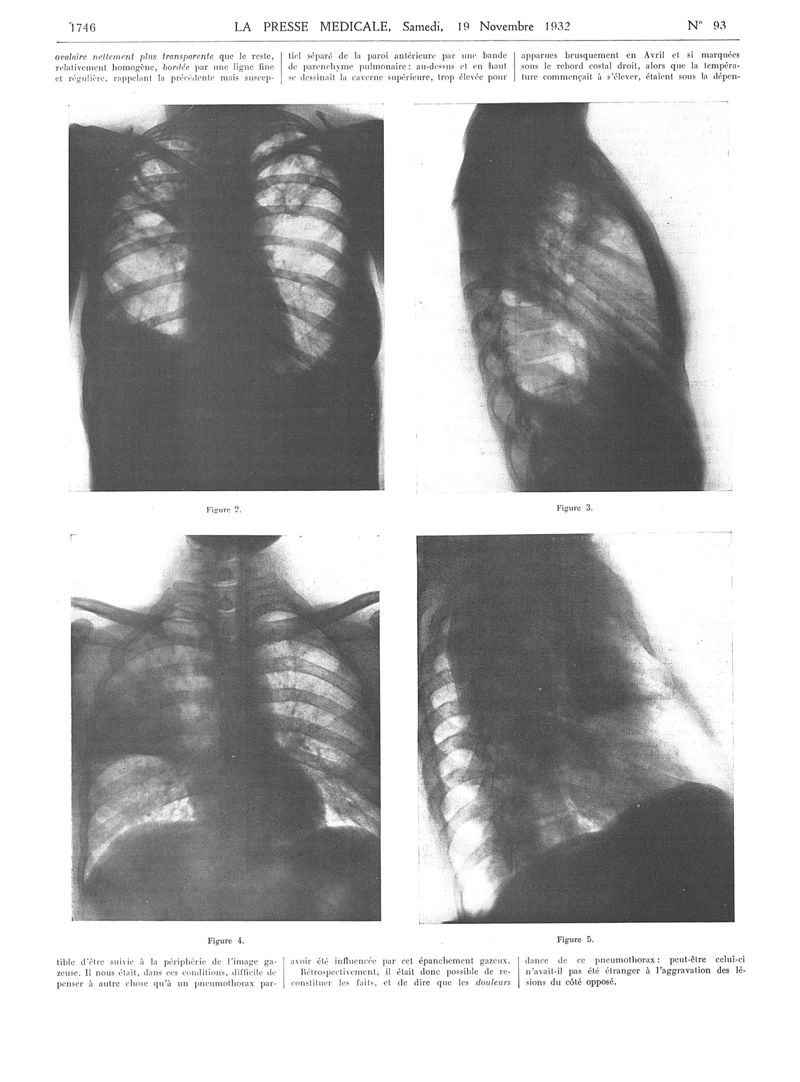

La Presse médicale - [Articles originaux]

1932, Articles originaux. - Masson et Cie, 1932.